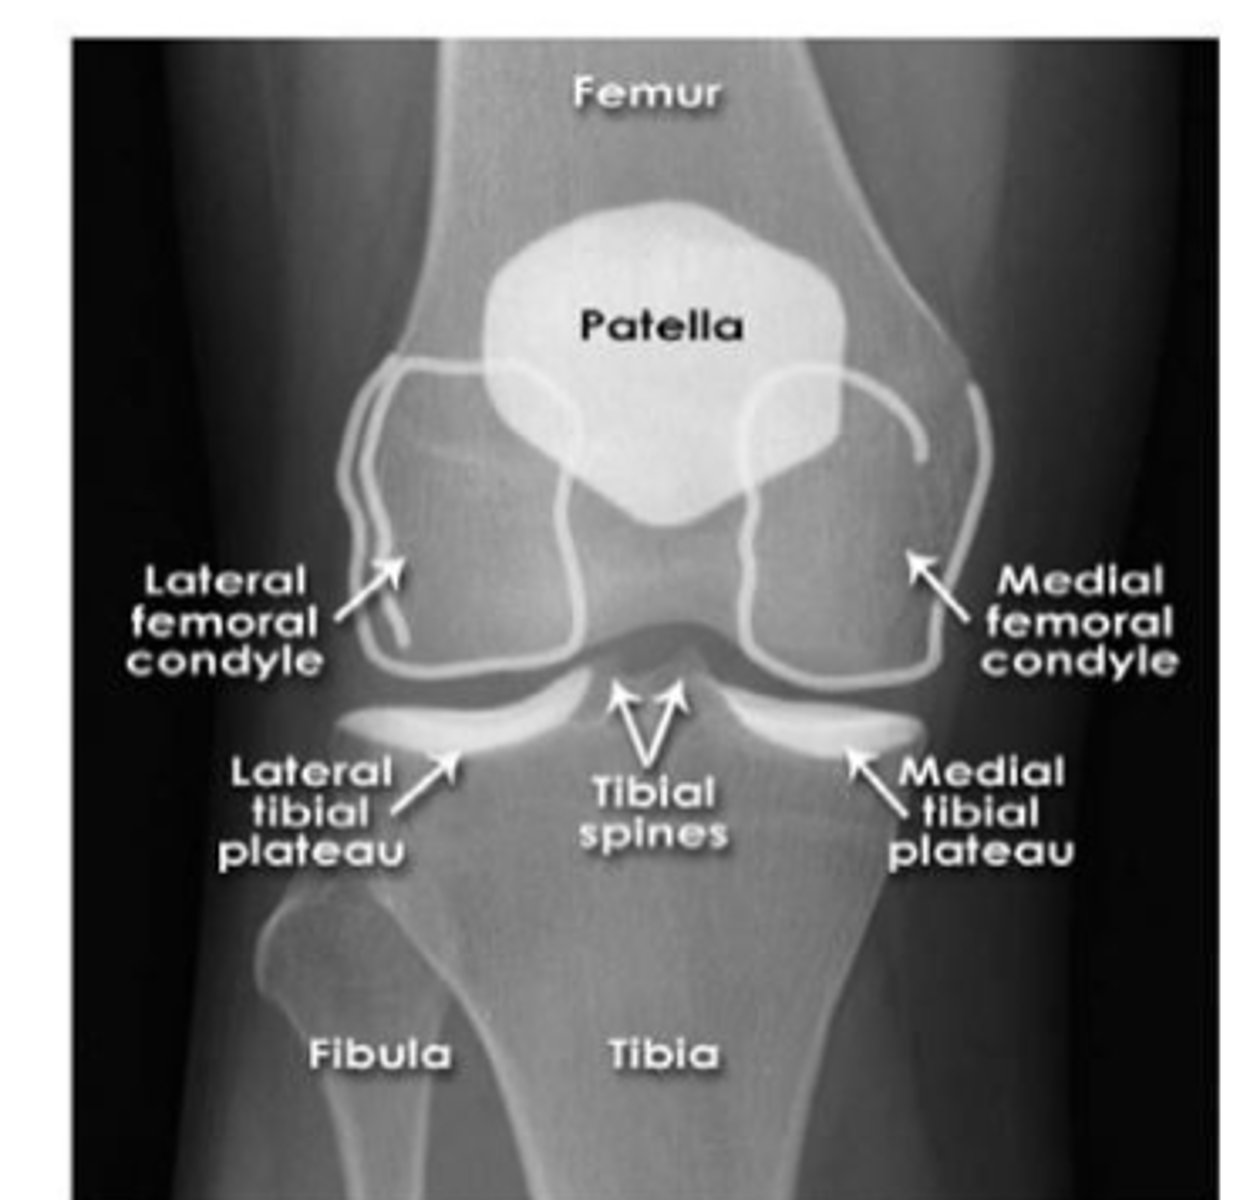

knee

knowt flashcard image